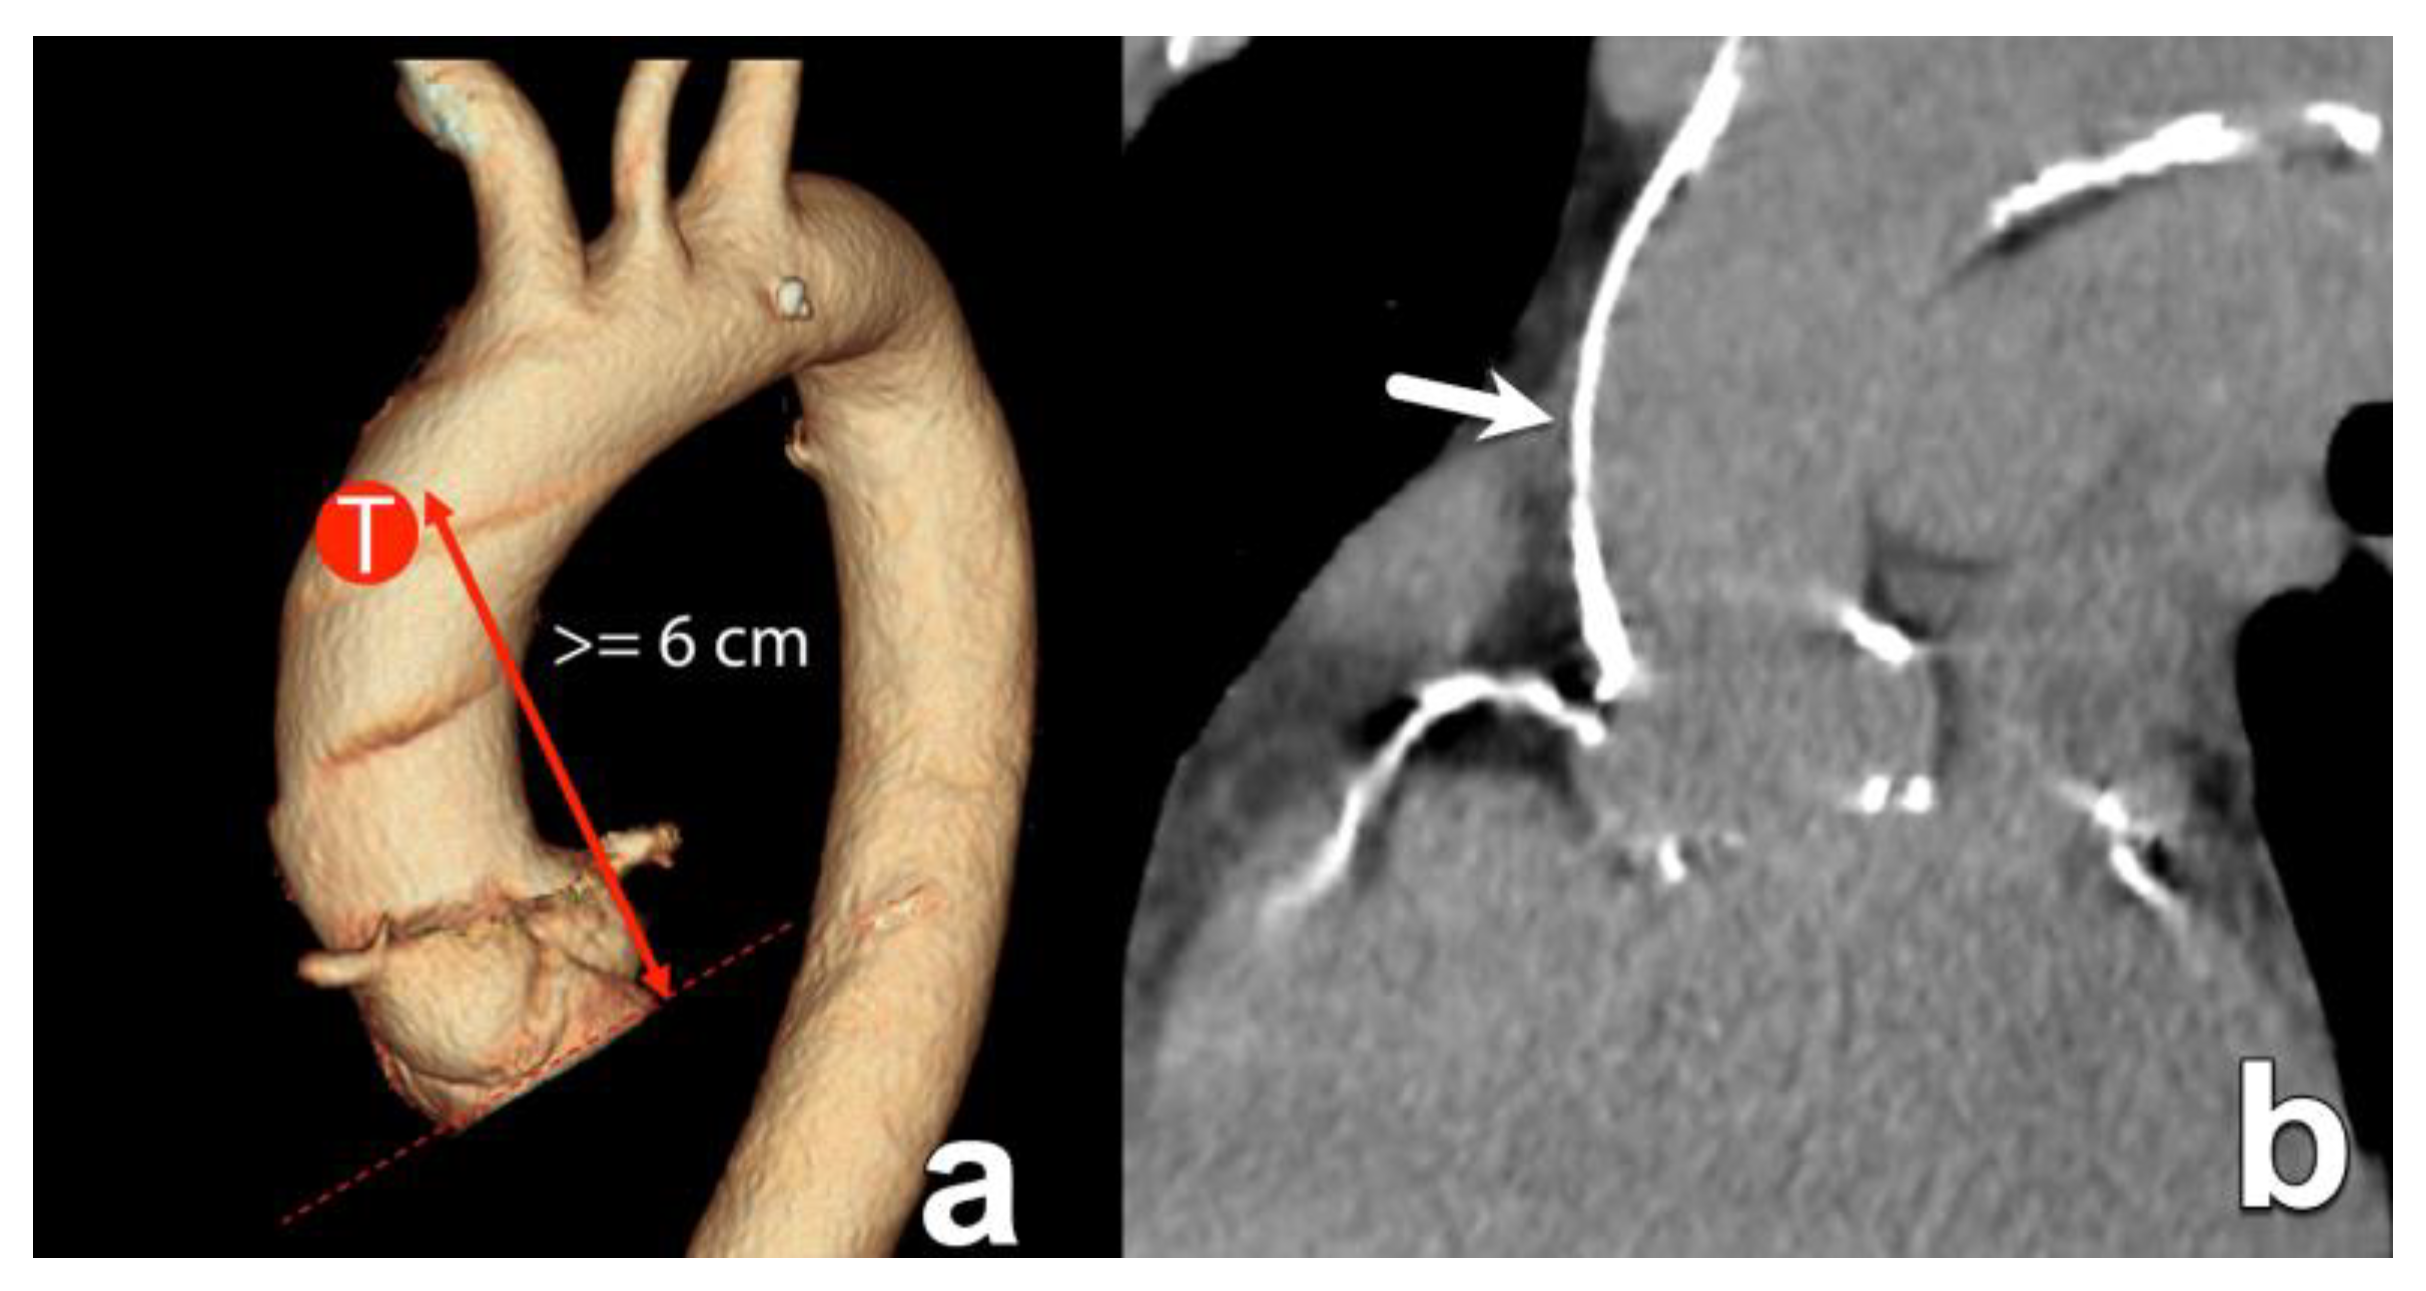

| Ascending aorta diameter and wall calcifications | Diameter at 40 mm above annulus Presence and severity of aortic wall calcification | For transaortic access, the landing zone is about 60 mm above the annular plane. |

| Transaortic | Direct access to the ascending aorta via mini-sternotomy. | Option when transfemoral route not possible. | More invasive. The amount/location of ascending aorta wall calcification is important, typically at about 6 cm above the annular plane. |